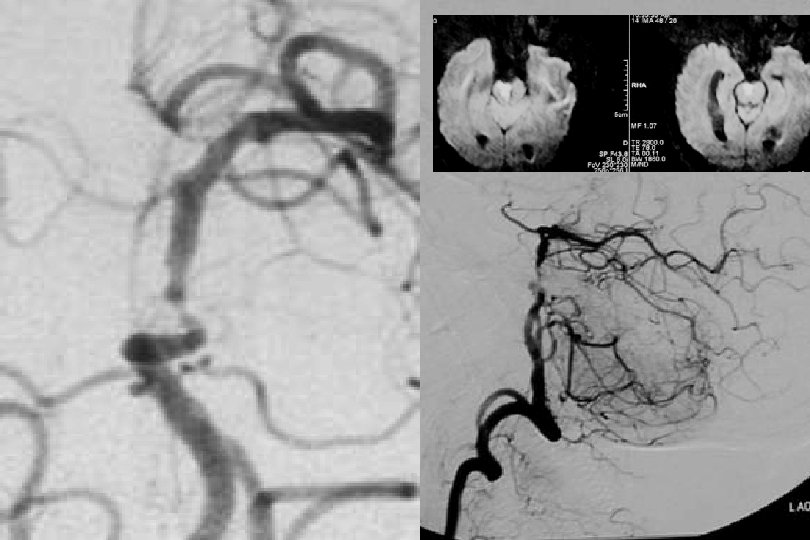

52 y kadın efektiv/test edilmiş ikili antiagregan ted altında iken multipl TIA Basit PTA sonrası

1. Yıl kontrol

1 yıl kontrol PTA Sonrası

71 y kadın hasta En iyi medikal tedavi altında post fossa iskemik ataklara neden olan baziler stenoz

PTA sonrası

. . 6 mm Solitaire ile Stentleme sonrası